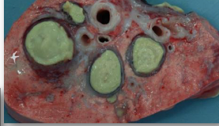

Which condition is represented here?

A

Caseous lymphadenitis

23

Q